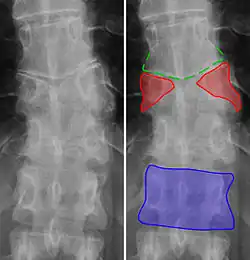

Lumbarization of sacral vertebra 1, seen as 6 vertebrae that do not connect to ribs.

Lumbarization is an anomaly in the spine. It is defined by the nonfusion of the first and second segments of the sacrum. The lumbar spine subsequently appears to have six vertebrae or segments, not five. This sixth lumbar vertebra is known as a transitional vertebra. Conversely the sacrum appears to have only four segments instead of its designated five segments. Lumbosacral transitional vertebrae consist of the process of the last lumbar vertebra fusing with the first sacral segment. [1] While only around 10 percent of adults have a spinal abnormality due to genetics, a sixth lumbar vertebra is one of the more common abnormalities. [2]

Sacralization of the L5 vertebra is seen at the lower right of the image.

Sacralization of the fifth lumbar vertebra (or sacralization) is a congenital anomaly, in which the transverse process of the last lumbar vertebra (L5) fuses to the sacrum on one side or both, or to ilium, or both. These anomalies are observed in about 3.5 percent of people, and it is usually bilateral but can be unilateral or incomplete (ipsilateral or contralateral rudimentary facets) as well. Although sacralization may be a cause of low back pain, it is asymptomatic in many cases (especially bilateral type). Low back pain in these cases most likely occurs due to biomechanics. In sacralization, the L5-S1 intervertebral disc may be thin and narrow. This abnormality is found by X-ray.